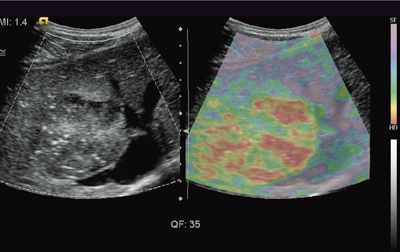

ストレインイメージングは,外部より力を加えて,各部がどれだけ形や位置を変えるかを測定して得ることができる。最初に開発されたのが,超音波プローブを手で押すことで体表から組織を圧迫する方法(Elasticity Imaging)である。乳腺領域ではこうした用手的圧迫が比較的容易であるため,Elasticity Imagingは,腫瘍の鑑別に多く利用されるようになってきた。しかし腹部領域では,対象が深部にあるため,体表からの圧迫が十分に作用せず,Elasticity Imagingが難しくなる。そこでシーメンスの“eSie Touch Elasticity Imaging”では,演算プロトコルの工夫によってきわめて小さな力(プローブを持つ手の自然なわずかな揺れや,心拍動による臓器の動きなど)で機能することに成功し,腹部領域にも適用できるようになった(図1)。

図1 eSie Touch Elasticity Imagingによる臨床例:転移性肝がん